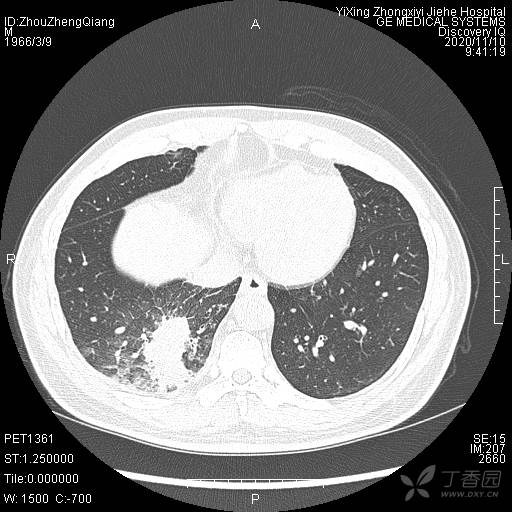

简要病史:咳嗽、咳痰,体重减轻5Kg+。

辅助检查:CT提示:右下肺占位伴周围炎症,CA待排,右侧少许胸腔积液。

临床诊断:右肺癌?待进一步检查。